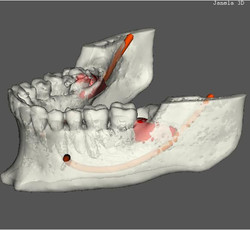

Caso 1: Anquilose de ATM

Paciente com assimetria, limitação de abertura bucal. Observa-se união óssea da porção posterior e lateral do côndilo ao esfeóide e zigomático.

Caso 3: Fratura de ATM

Paciente com história clínica de trauma. Fratura no côndilo direito com deslocamento do fragmento para medial e deslogamento do côndilo para lateral da cavidade articular.

Caso 4: Lesão Patológica

O exame tomográfico permite a exata localização e extensão do tumor bem como a identificação de áreas com destruição da cortical e a localização de lesões satélites.